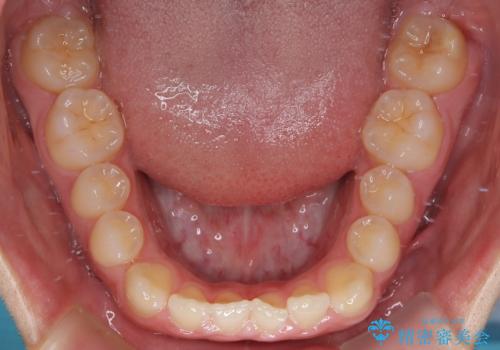

- 「前歯のすきっ歯が気になる」「食べ物が歯の間に詰まりやすい」とのお悩みで来院された20代男性の患者様です。

歯と歯の間に隙間がある**空隙歯列(すきっ歯)**は、見た目の問題だけでなく、食片圧入による歯肉の腫れや、隣接面う蝕のリスク増加につながることがあります。

診査により舌突出癖が認められました。この癖は、すきっ歯の原因となるだけでなく、矯正後の後戻りリスクを高めます。

そこで矯正治療と並行して**MFT(口腔筋機能療法)**を実施し、舌や口周囲筋の正しい使い方を習得していただきました。